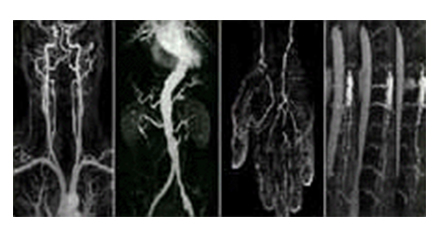

• 혈관 강조 영상(Magnetic Resonance Angiogram) 이미지

혈관 강조 영상

(Magnetic Resonance Angiogram)

특수한 영상기법을 이용하여 인체 내의 미세한 혈관까지도 묘출이 가능합니다.

• 전신 혈관 자기 공명 영상(Whole Body Angiogram) 이미지

전신 혈관 자기 공명 영상

(Whole Body Angiogram)

특수한 영상기법을 이용하여 인체 내의 모든 혈관까지도 묘출이 가능합니다.